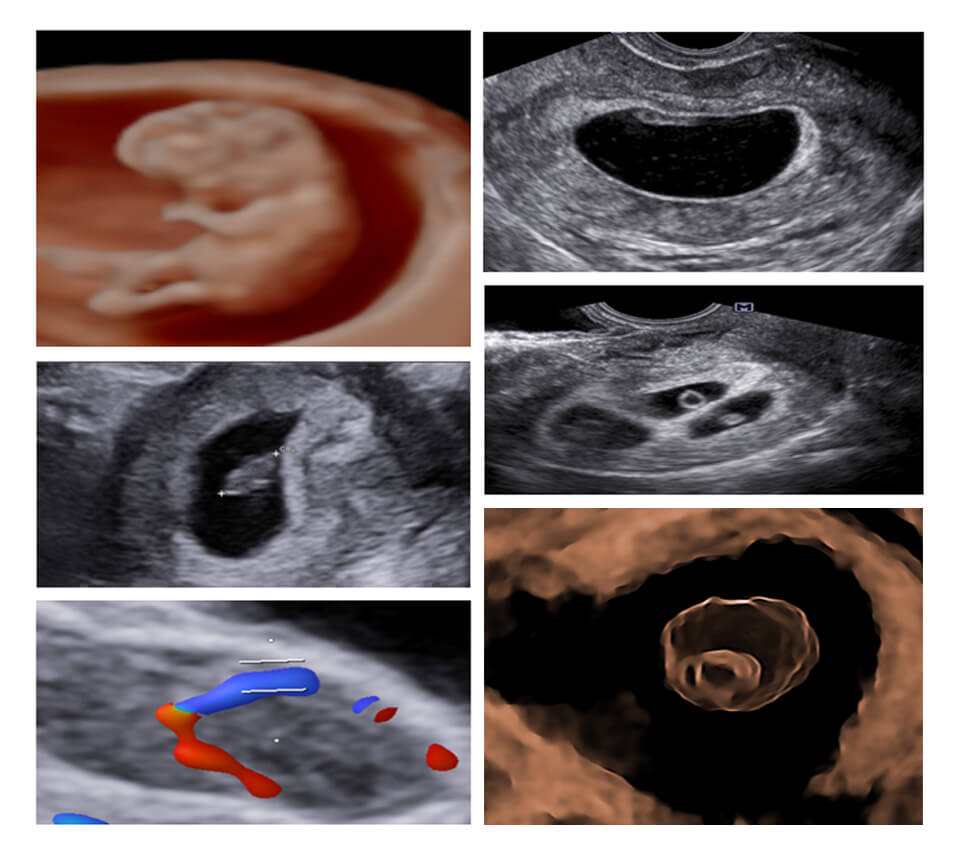

EARLY PREGNANCY ULTRASOUND : WHAT’S NEW

FIRST TRIMESTER (11-14 WEEKS) USG

CDC : PREGNENCY (04-14)

04-10 WEEKS

CORPUS LUTEUM

RPOC

MISSED

MOLAR

11-14 WEEKS